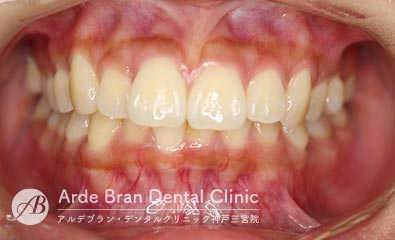

- 叢生/八重歯/歯のがたつき(20代女性 治療期間2年)

- 上下の犬歯の突出と歯のがたつきを主訴に来院されました。特に上下ともに犬歯が大きく前に出ており、噛み合わせに悪影響を及ぼしている状態でした。歯列のスペース不足が顕著であったため、上下左右の第一小臼歯を4本抜歯し、適切な歯列を確保する方針としました。治療では、上下の犬歯を正しい位置へ誘導しながら、全体の噛み合わせを調整。歯列のアーチを整え、前歯のねじれやガタつきも改善しました。治療後は、上下の犬歯が適切な位置に収まり、口元のラインがすっきりと改善。歯並びだけでなく、噛み合わせや清掃性の向上にもつながり、機能的で美しい口元を実現しました。

- 治療前

- 治療後

| 装置名 | インビザライン(マウスピース矯正) |

| 抜歯非抜歯 | 4本抜歯 |

| 治療期間 | 2年 |

| 費用 | インビザラインフル72万円+TAX |